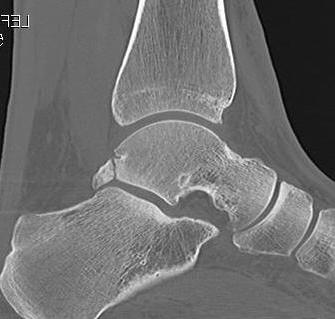

CT

Os trigonum

Fractured Stieda process

Os trigonum with osteochondral fracture posterior tibia